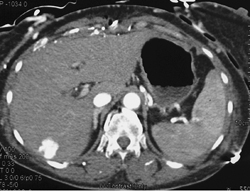

Hepatoma- Multifocal